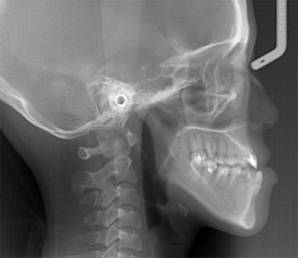

放射检查:一般包括X线头影测量片、曲面体层片和CBCT(锥束CT)。有时还包括其他放射检查,比如螺旋CT等。通过放射检查,医生可以看到骨骼及牙齿的形态、位置及发育状况,以及是否有牙体、根尖周、牙周疾病等,从而评估是否需要正畸治疗、进行何种治疗。

(摘自“第三章第一节正畸的基本知识”)

头影测量片(上)、曲面体层片(中)和锥束CT(下)